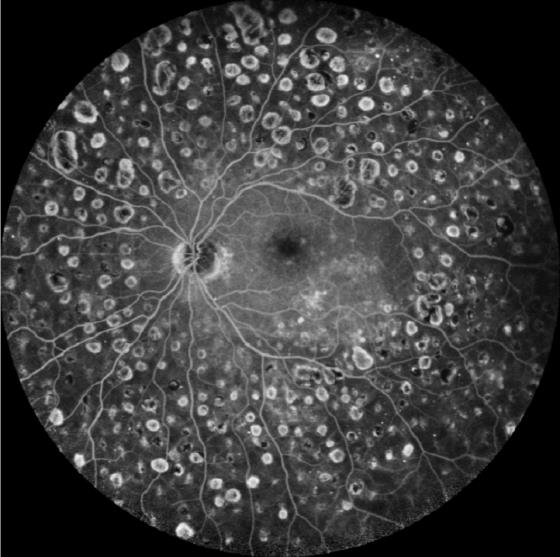

Εικόνα φλουοροαγγειογραφίας αμφιβληστροειδούς μετά από argon φωτοπηξία